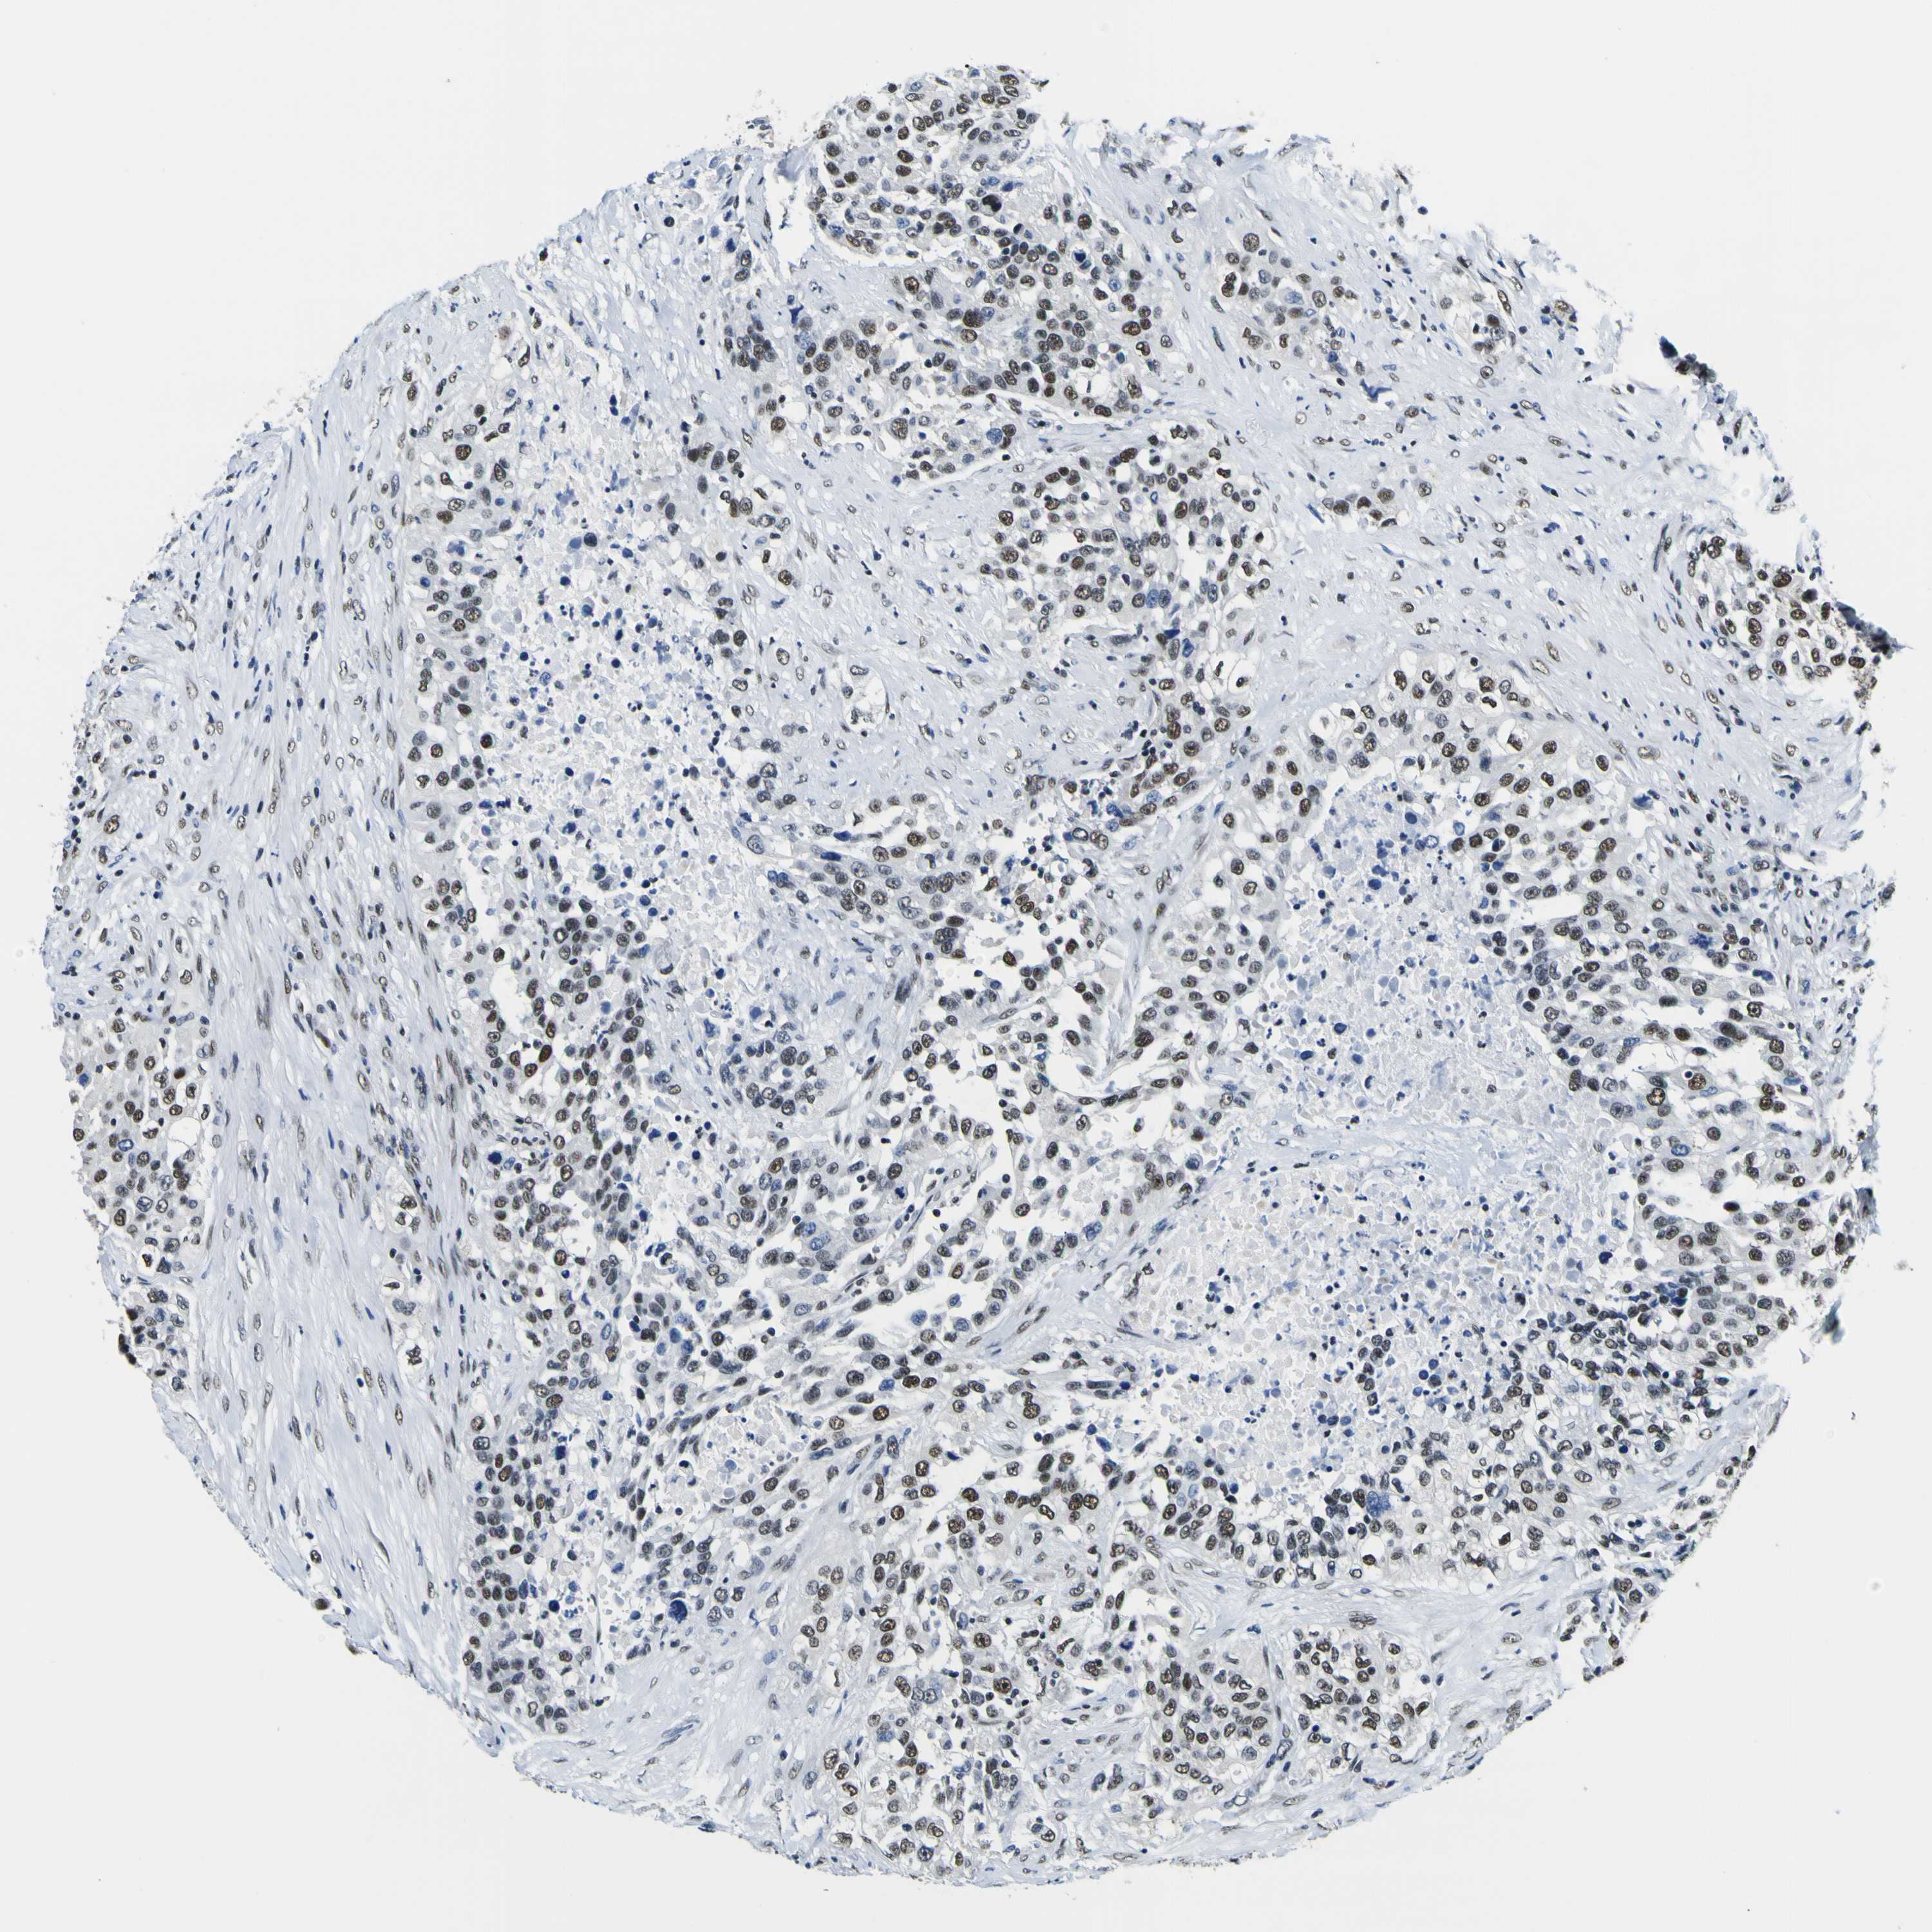

UROTHELIAL CANCER - Protein expressioni

A mouse-over function shows sample information and annotation data. Click on an image to view it in a full screen mode. Samples can be filtered based on level of antibody staining by selecting one or several of the following categories: high, medium, low and not detected. The assay and annotation is described here.

Note that samples used for immunohistochemistry by the Human Protein Atlas do not correspond to samples in the TCGA dataset.

Antibody stainingi

Antibody staining in the annotated cell types in the current human tissue is reported as not detected, low, medium, or high, based on conventional immunohistochemistry profiling in selected tissues. This score is based on the combination of the staining intensity and fraction of stained cells.

Each image is clickable and will lead to virtual microscopy that enables deeper exploration of all samples and also displays staining intensity scores, fraction scores and subcellular localization as well as patient and tissue information for each sample.

Antibody HPA001853

Antibody HPA012292

Antibody CAB000330

Staining

High

Medium

Low

Not detected

Intensity

Strong

Moderate

Weak

Negative

Quantity

>75%

75%-25%

<25%

None

Location

Nuclear

Cytoplasmic/membranous

Cytoplasmic/membranous,nuclear

Urothelial carcinoma, High grade

Urothelial carcinoma, Low grade